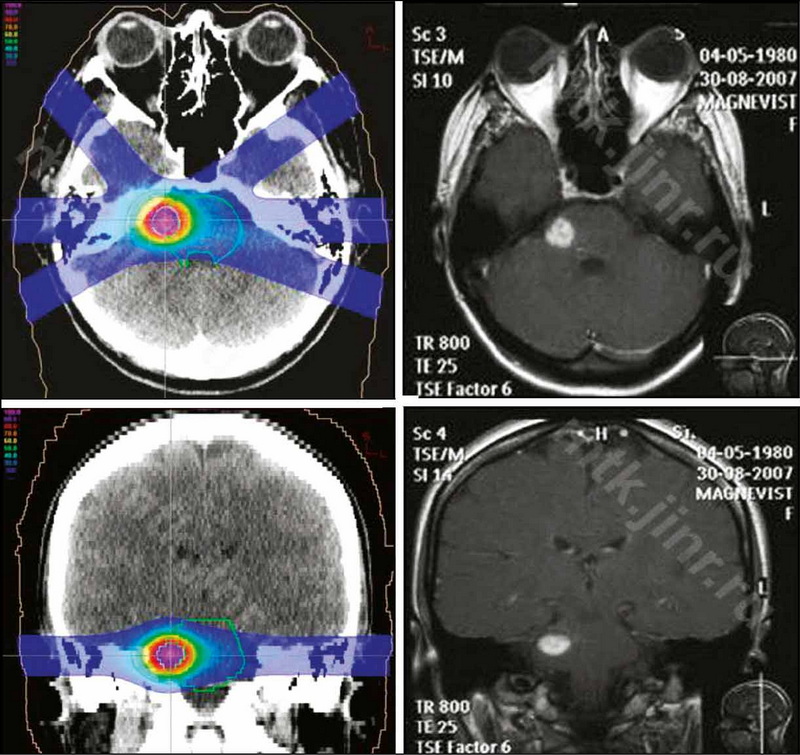

Кавернозные мальформации головного мозга благодаря развитию современных методов нейровизуализации являются в последние годы всё чаще обнаруживаемой патологией. Несмотря на доброкачественный характер течения в большинстве случаев, данные образования могут приводить к развитию судорожного синдрома и серьёзным неврологическим нарушениям. Как правило, причинами клинических симптомов являются кровоизлияния в структуру каверном и окружающую паренхиму головного мозга. Выбор тактики ведения пациентов с кавернозными мальформациями головного мозга зависит от типа мальформации, её размеров, локализации, наличия повторных кровоизлияний и клинической картины.

Данный обзор литературы посвящён современным методам лечения кавернозных мальформаций головного мозга, в частности хирургическим подходам. В случаях глубинного расположения очагов в функционально значимых зонах головного мозга, для которых характерен максимальный риск осложнений при хирургическом вмешательстве, альтернативными выступают методы лучевой терапии, такие как стереотаксическая радиохирургия, протонная терапия. Рассматриваются возможности, эффективность и безопасность стереотаксического радиохирургического лечения, использование протонной терапии в лечении кавернозных мальформаций. Выявлены преимущества лучевых методов лечения кавернозных мальформаций.